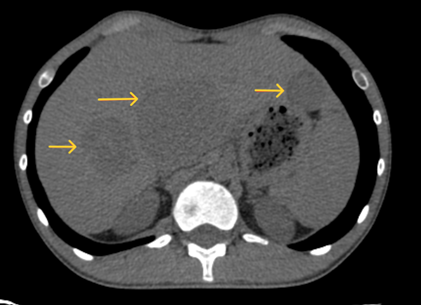

- Chụp CT ổ bụng không tiêm thuốc: Tiểu khung lệch trái có khối tỷ trọng tổ chức ~30HU kích thước mm 74x43x43mm, xung quanh có vài hạch kích thước lớn nhất 18x12mm. Gan kích thước bình thường, bờ đều. Nhu mô hạ phân thùy trước, sau và gan tái có các khối giảm tỷ trọng kích thước lần lượt 62x48mm, 40x34mm, 27x23mm, bờ đều rõ.

Hình 2: Hình ảnh chụp CT ổ bụng có khối vùng tiểu khung lệch trái chèn ép gây giãn đài bê thận - niệu quản trái (mũi tên vàng)

Hình 3: Hình ảnh chụp CT ổ bụng có các khối giảm tỷ trọng ở nhu mô gan 2 bên, bờ đều rõ (mũi tên vàng)